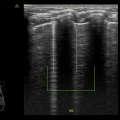

Ecografo POC - Venue GO

GE Venue Go è la versione intermedia della famiglia POC Venue.

Il modulo ecografico carrellato si può separare e usare come portatile. Ha monitor touch da 15,6″, imaging clinico chiaro e strumenti automatici basati su intelligenza artificiale per valutazioni rapide e supporto decisionale in ambienti critici, batterie con autonomia fino a 2 h e superficie facile da pulire per la gestione delle infezioni. È progettato per movimentarsi agilmente nel reparto, con gestione intelligente dei cavi, uso intuitivo e resistenza agli urti.